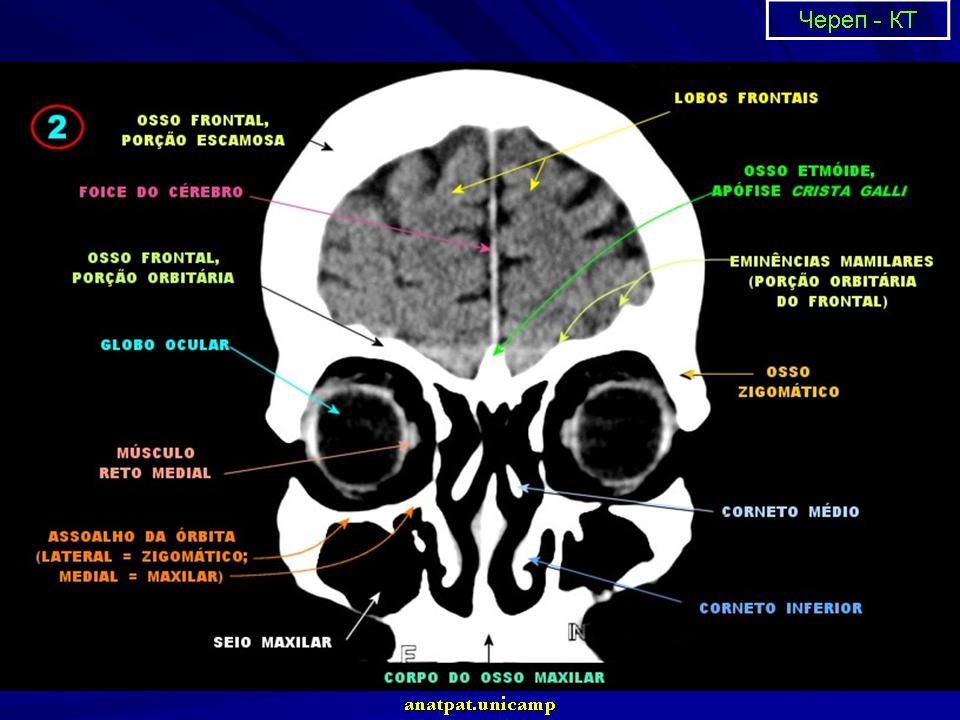

Нормальная КТ - анатомия головного мозга.

1.ki_.slayd1_.jpg2.ki_.slayd2_.jpg3.ki_.slayd3_.jpg4.ki_.slayd4_.jpg5.ki_.slayd5_.jpg6.ki_.slayd6_.jpg7.ki_.slayd7_.jpg8.ki_.slayd8_.jpg11.ki_.slayd9_.jpg12.ki_.slayd10.jpg13.ki_.slayd11.jpg14.ki_.slayd12.jpg15.ki_.slayd13.jpg16.ki_.slayd14.jpg17.ki_.slayd15.jpg18.ki_.slayd16.jpg21.ki_.slayd17.jpg22.ki_.slayd18.jpg23.ki_.slayd19.jpg24.ki_.slayd20.jpg25.ki_.slayd21.jpg26.ki_.slayd22.jpg27.ki_.slayd23.jpg28.ki_.slayd24.jpg